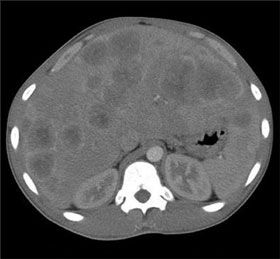

A CT scan of the abdomen (shown) revealed massive hepatomegaly with several solid lesions in the liver and a large mass in the pancreas. All abdominal organs, including the stomach, spleen, and kidneys, were compressed by the enlarged liver.